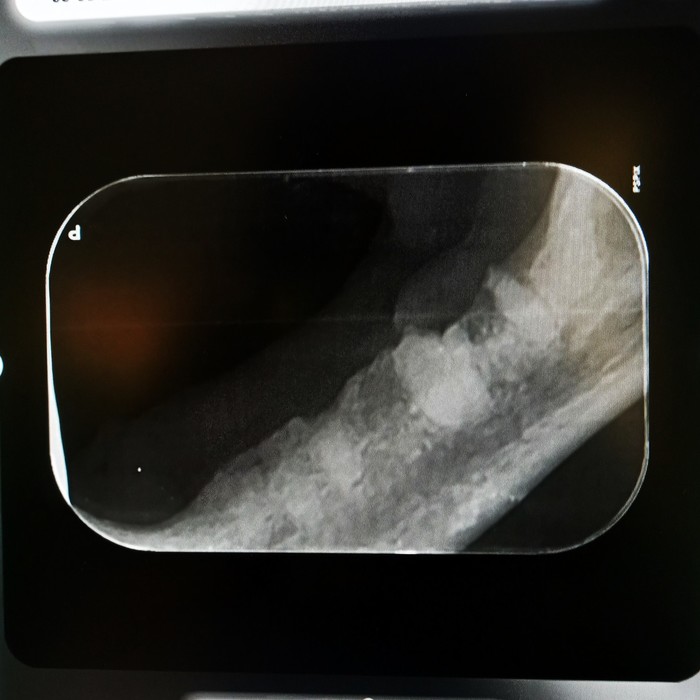

Rentgeny zubů se využívají na zobrazení hlubších vrstev zubů, kořenového systému zubů, posouzení parodontu a čelistních kostní.

Při rentgenologickém vyšetření posuzujeme následující struktury:

Korunka zubu: přítomnost a celistvost skloviny, šířka dentinu a jeho případné patologie, šířka dřeňové dutiny, celistvost zubu, při frakturách rozsah zlomenin, hledáme resorptivní léze, kazy, částečné/úplné fraktury, změny tvaru a celistvosti korunky

Krček zubu: celistvost krčku, resorptivní léze, kazy, fraktury

Kořen zubu: posouzení cementu na povrchu zubů, dentinu, dřeňové dutiny, fraktur kořenů, tvaru kořenů a jeho případných výběžků, přítomnosti tzv. pulpálních kamenů, osteoresorptivních lézí

Čelist: posouzení případných periapikálních reakcí, přítomnosti, úbytku či změny struktury alveolární kosti, přítomnost zlomenin čelisti či nádorového procesu, ne/přítomnost některých zubů

kořenové anomálie

kořeny mléčných zubů

periapikální absces

polámané kořeny v čelisti

vstřebávající se kořen špičáku

resorptivní léze